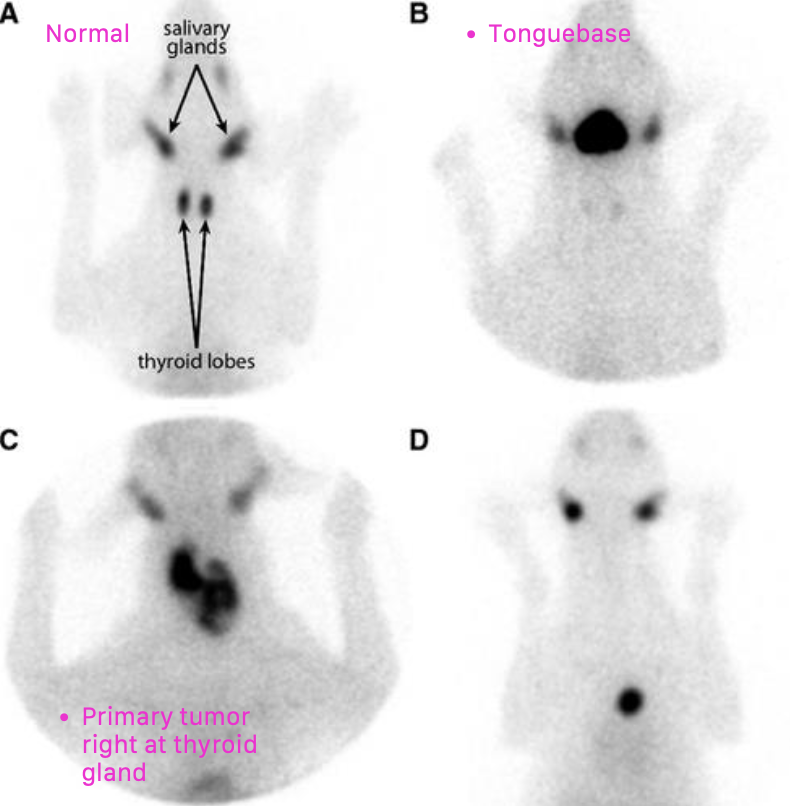

how is canine thyroid carcinoma diagnosed/staged?

5. scintigraphy

what is the location of thyroid tumors in dogs?

~60% of cases have bilateral disease

can also have ectopic thyroid neoplasia (can occur anywhere from base of tongue to base of the heart)